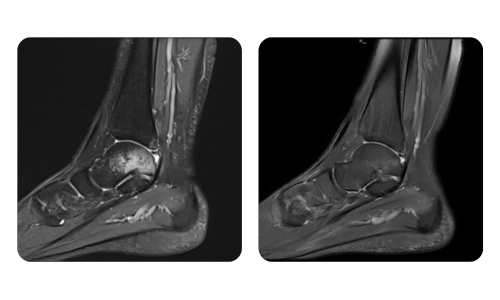

I progressi dei nostri pazienti, misurati prima e dopo la terapia iperbarica, riflettono l'efficacia e l'impatto positivo del trattamento. Scopri i risultati documentati della terapia iperbarica presso la clinica Hyperbarium Oradea, basati su valutazioni cliniche e dati oggettivi che evidenziano miglioramenti significativi in diverse condizioni.